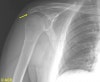

Shoulder X-ray의 Normal variation2016-10-12카테고리 51원본 보기1. Os acromiale 2. Rhomboid fossa 3. Bicipital groove ← 이전 글Acromion index다음 글 →족하수(Foot drop) : 갑자기 발목이 올라가지 않아요같은 카테고리 글2017-05-06Sulcus sign : 하방 불안정성을 조사하는 검사2017-05-05부하 전위 검사(Load and Shift Test) : 전방 불안정성을 조사하는 검사2017-05-04어깨 전방 불안정 검사(Anterior apprehension test) : 전방 불안정성을 조사하는 검사← 전체 글로 돌아가기